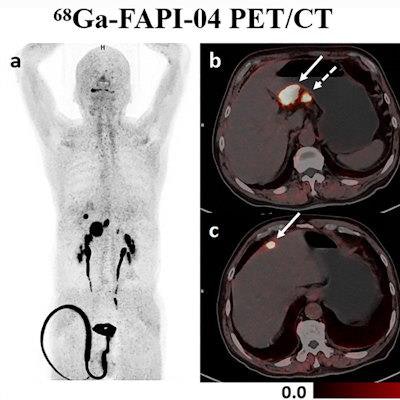

The authors reported that Ga-68 FAPI-04 PET/CT detected more primary lesions (90.3% vs. 77.4%, p = 0.008) and peritoneal metastases (91.7% vs. 41.7%, p = 0.031) and demonstrated higher SUVmax and TBR values (p < 0.001) of primary lesions compared to F-18 FDG PET/CT.

Dual-tracer PET/CT significantly improved the diagnostic sensitivity for the detection of distant metastases, compared with stand-alone F-18 FDG (97.1% vs. 73.5%, p = 0.008) or Ga-68 FAPI-04 (97.1% vs. 76.5%, p = 0.016) PET/CT.

Treatment strategies were then changed in nine patients following Ga-68 FAPI-04 and F-18 FDG dual-tracer PET/CT. Nevertheless, Ga-68 FAPI-04 uptake was primarily influenced by the size and invasion depth of the tumor. Both Ga-68 FAPI-04 and F-18 FDG PET/CT showed limited sensitivity for detecting early gastric cancer (37.5% vs. 25%, p > 0.05).